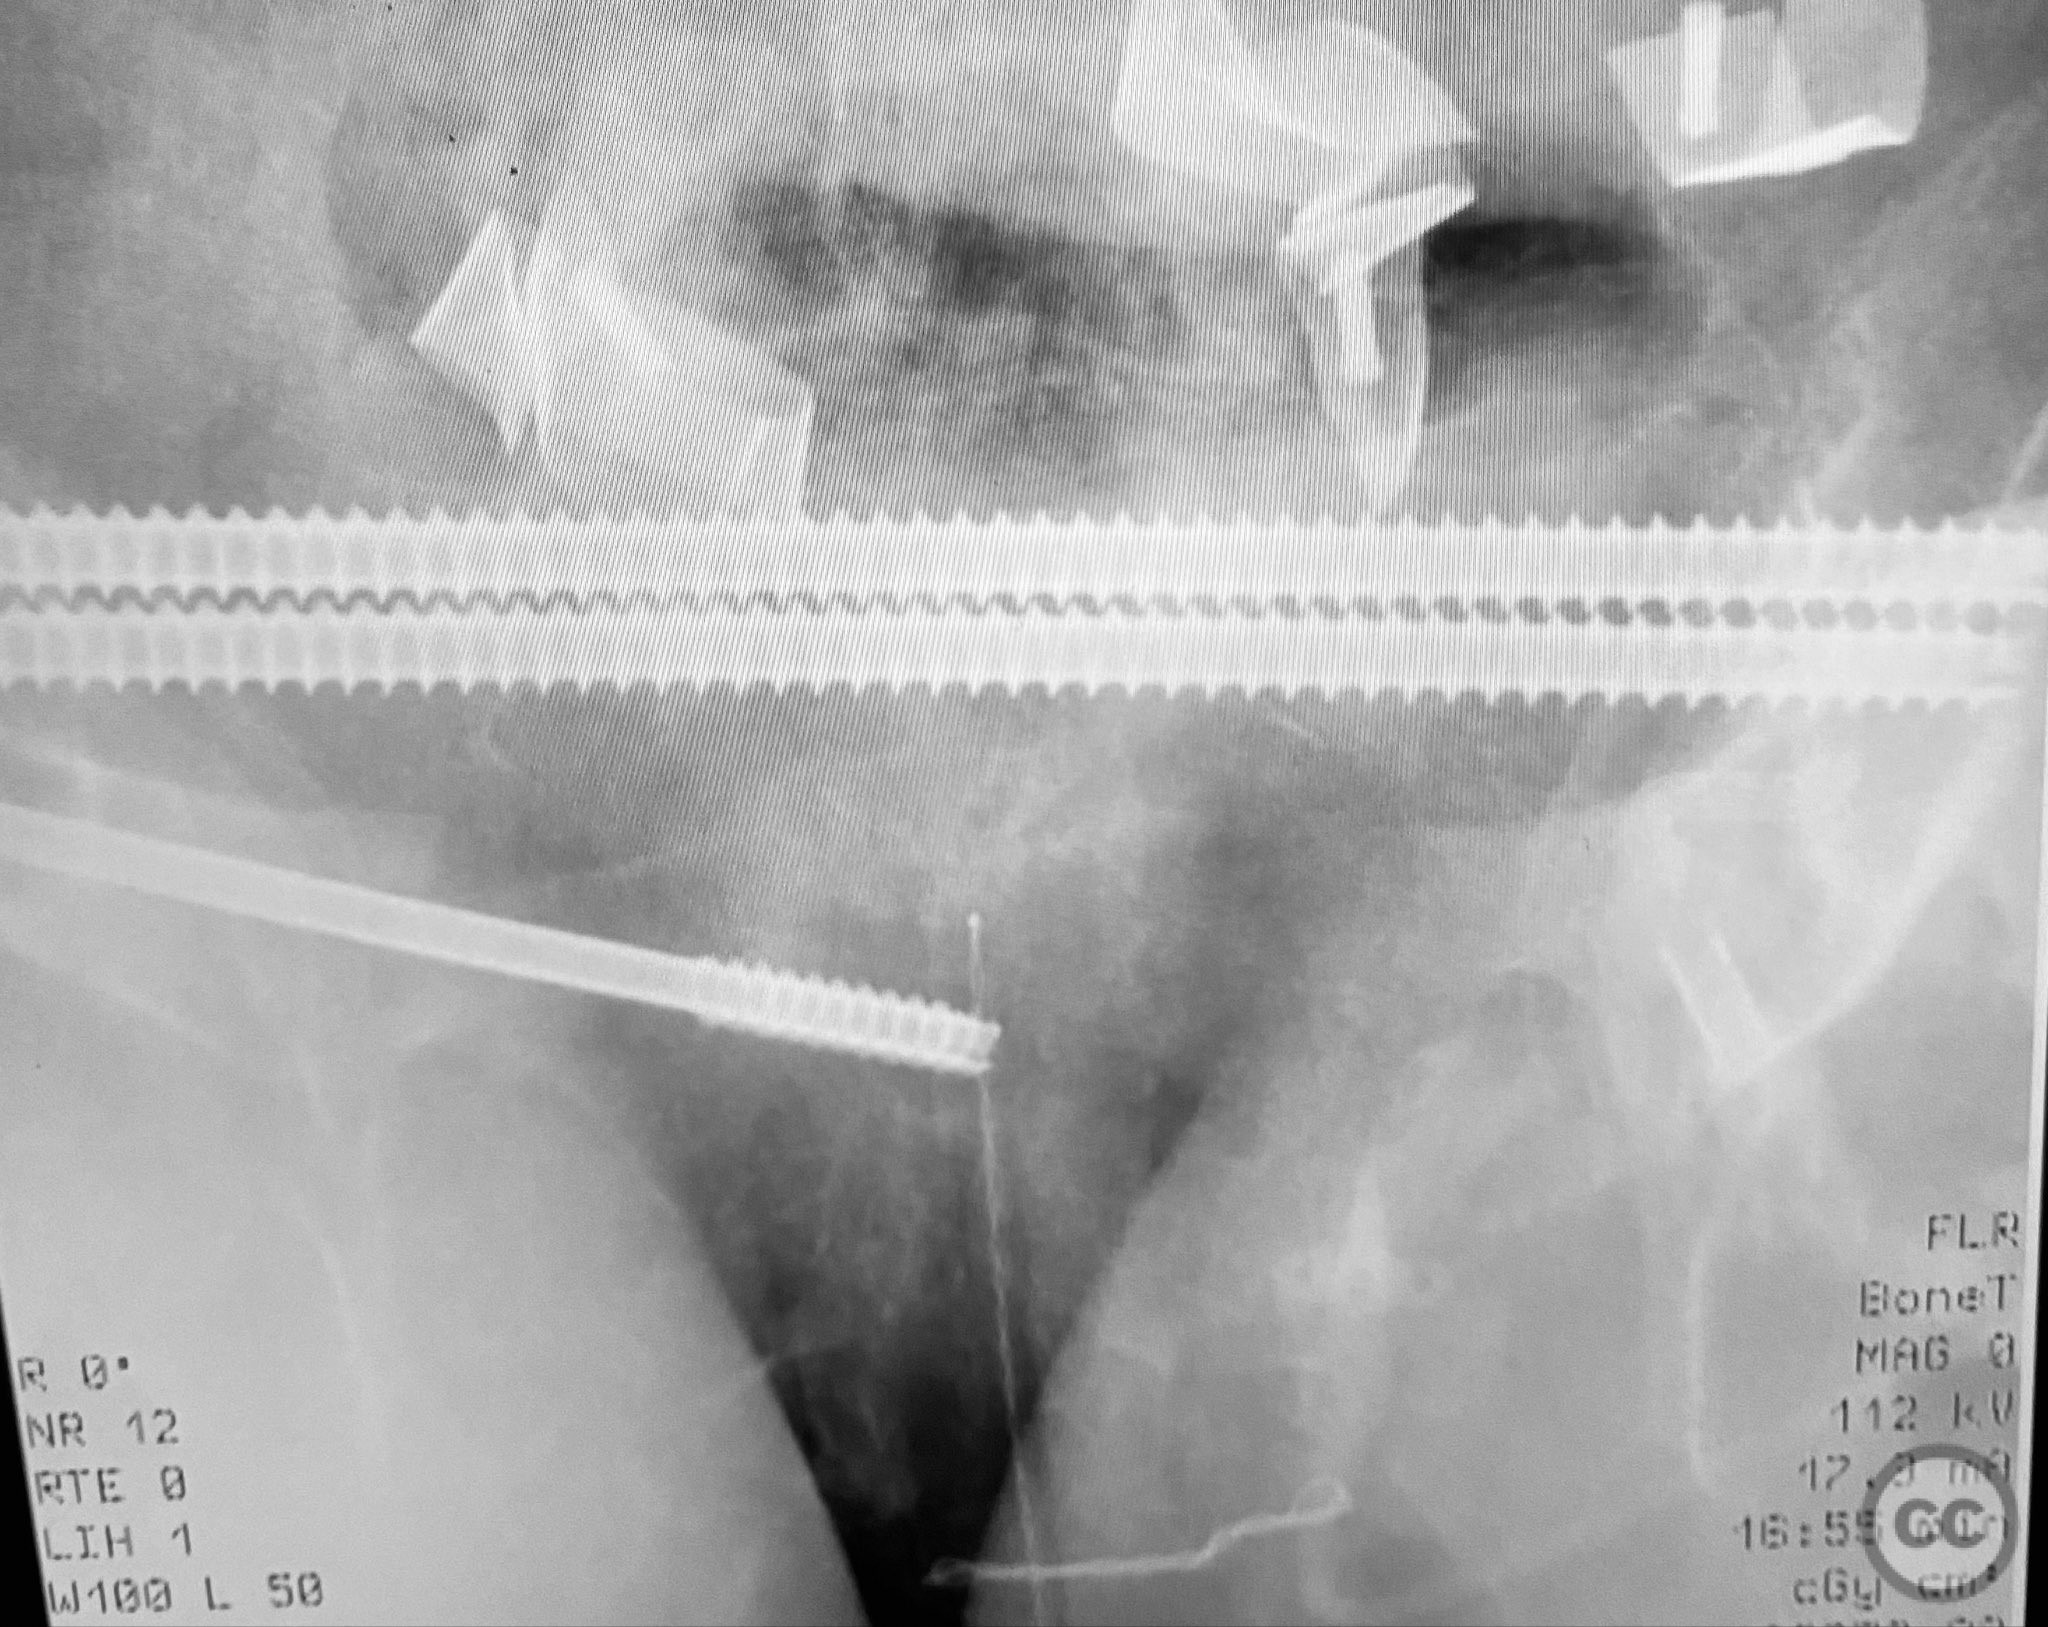

Planning remarks:  The preoperative plan included early closed reduction maneuvers under fluoroscopic guidance, percutaneous stabilization of the pelvic ring with cannulated screws, and intramedullary nailing of the proximal femur. The anatomical approach for pelvic fixation was percutaneous iliosacral screw placement; for the femur, a standard antegrade intramedullary nailing technique was planned.

Anatomical surgical approach:  Percutaneous iliosacral screw fixation was performed through small lateral gluteal incisions, with blunt dissection to the outer table of the os ilium. Under fluoroscopic guidance, guidewires were advanced across the sacroiliac joint into the S1 body, followed by cannulated screw insertion. For the proximal femur, a longitudinal incision was made proximal to the greater trochanter, splitting the fascia lata and gluteus medius fibers to access the piriformis fossa. A guidewire was inserted into the medullary canal, followed by sequential reaming and insertion of an intramedullary nail.

Intraoperative imaging was challenging due to osteopenic bone, fracture comminution, and interference from abdominal packing. Accurate identification of safe osseous corridors for iliosacral screw placement required multiple fluoroscopic projections and careful attention to pelvic landmarks. Bone quality necessitated cautious screw advancement to avoid iatrogenic cortical breach. After pelvic fixation, intramedullary nailing of the proximal femur proceeded without complication. Abdominal packing was removed and laparotomy wound closed after skeletal stabilization. Early mechanical stabilization of both pelvic and femoral injuries was prioritized to optimize survivability in this multiply injured elderly patient.